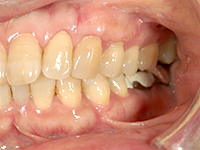

結合組織移植術

右上3番、4番の歯の根が露出していたため、上顎の裏側から結合組織を移植しました。

他の箇所とかわりなく、きれいな歯ぐきになりました。

上顎裏側の結合組織を摘出しています。術後の傷も、きれいに治りました。